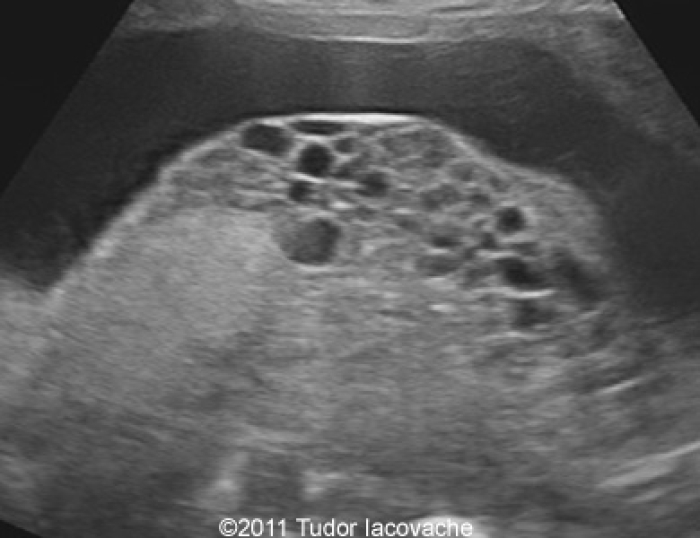

De diagnose wordt in de meeste gevallen gesteld tijdens de eerste echo, meestal rond de 10 tot 12 weken. Voor veel vrouwen is dit het moment waarop de vreugde omslaat in grote bezorgdheid. De echoscopist ziet op het scherm namelijk geen foetus of dooierzak, maar een beeld dat medisch wordt omschreven als een ‘sneeuwstormbeeld’. Dit zijn de talloze kleine blaasjes die de baarmoeder vullen.

fNaast de echo is een uitgebreid bloedonderzoek noodzakelijk. Hierbij wordt specifiek gekeken naar de waarde van het hCG-hormoon (humaan choriongonadotrofine). Bij een mola is deze waarde vaak vele malen hoger dan de referentiewaarden voor de duur van de zwangerschap. Om de diagnose honderd procent zeker te stellen, wordt na de ingreep het weggenomen weefsel altijd onderzocht door een patholoog. Deze specialist kan onder de microscoop precies zien of het een complete of een partiële mola betreft.